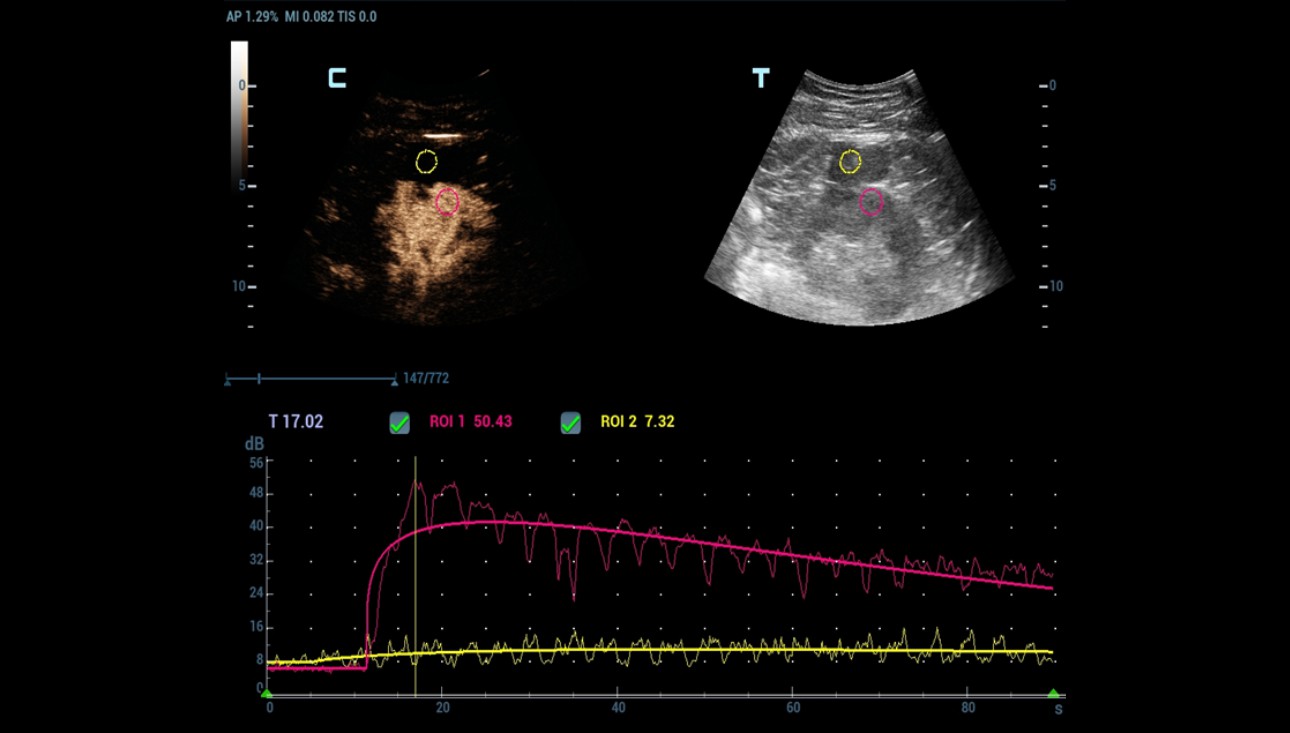

Quantitative analysis also confirmed the absence of enhancement within the cystic mass (Figure 6).

Figure 6: Contrast Imaging Quantification Analysis, red curve: the renal cortex, yellow curve: cystic mass.